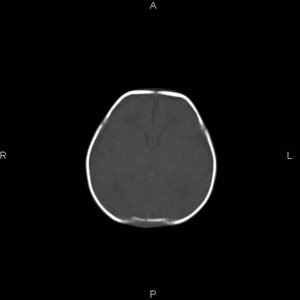

患者男,27天,出生后正常,今天中午在母亲怀里抱着吃奶在放下睡觉时发现后枕部慢慢出现一包块,来查头颅ct。无外伤史。包块内ct值47-51hu。请大家讨论。

皮下血肿,颅骨无缺如 ,颅缝无增宽。皮下血管破裂所因起。

头皮下血肿,局部枕骨略有凹陷

颅骨无缺损,骨缝无增宽.支持头皮血肿(血管破裂)